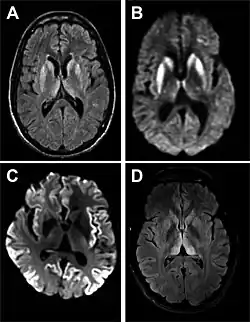

Through the image of MRI, the obvious precipitation of prion protein in the brain is visible.

• MRI with diffusion weighted inversion (DWI) and fluid-attenuated inversion recovery (FLAIR) shows a high signal intensity in certain parts of the cortex (a cortical ribboning appearance), the basal ganglia, and the thalami.[42] The most common presenting patterns are simultaneous involvement of the cortex and striatum (60% of cases), cortical involvement without the striatum (30%), thalamus (21%), cerebellum (8%) and striatum without cortical involvement (7%). In populations with a rapidly progressive dementia (early in the disease process), MRI has a sensitivity of 91% and specificity of 97% for diagnosing CJD.[46] The MRI changes characteristic of CJD may also be seen in the immediate aftermath (hours after the event) of autoimmune encephalitis or focal seizures.[42]

Imaging of the brain may be performed during medical evaluation, both to rule out other causes and to obtain supportive evidence for diagnosis. Imaging findings are variable in their appearance and also variable in sensitivity and specificity.[49] While imaging plays a lesser role in diagnosis of CJD,[50] characteristic findings on brain MRI in some cases may precede onset of clinical manifestations.[51]

Brain MRI is the most useful imaging modality for changes related to CJD. Of the MRI sequences, diffuse-weighted imaging sequences are most sensitive.[52] Characteristic findings are as follows:

• Focal or diffuse diffusion-restriction involving the cerebral cortex or basal ganglia. The most characteristic and striking cortical abnormality has been called "cortical ribboning" or "cortical ribbon sign" due to hyperintensities resembling ribbons appearing in the cortex on MRI.[53] The involvement of the thalamus can be found in sCJD, is even stronger and constant in vCJD.[54]

• Varying degree of symmetric T2 hyperintense signal changes in the basal ganglia (i.e., caudate and putamen), and to a lesser extent globus pallidus and occipital cortex.[50]

Signal hyperintensity in the caudate nucleus and putamen on diffusion-weighted and FLAIR MRI Often present Often absent

Pulvinar sign-bilateral high signal intensities on axial FLAIR MRI. Also, posterior thalamic involvement on sagittal T2 sequences Not reported Present in >75% of cases